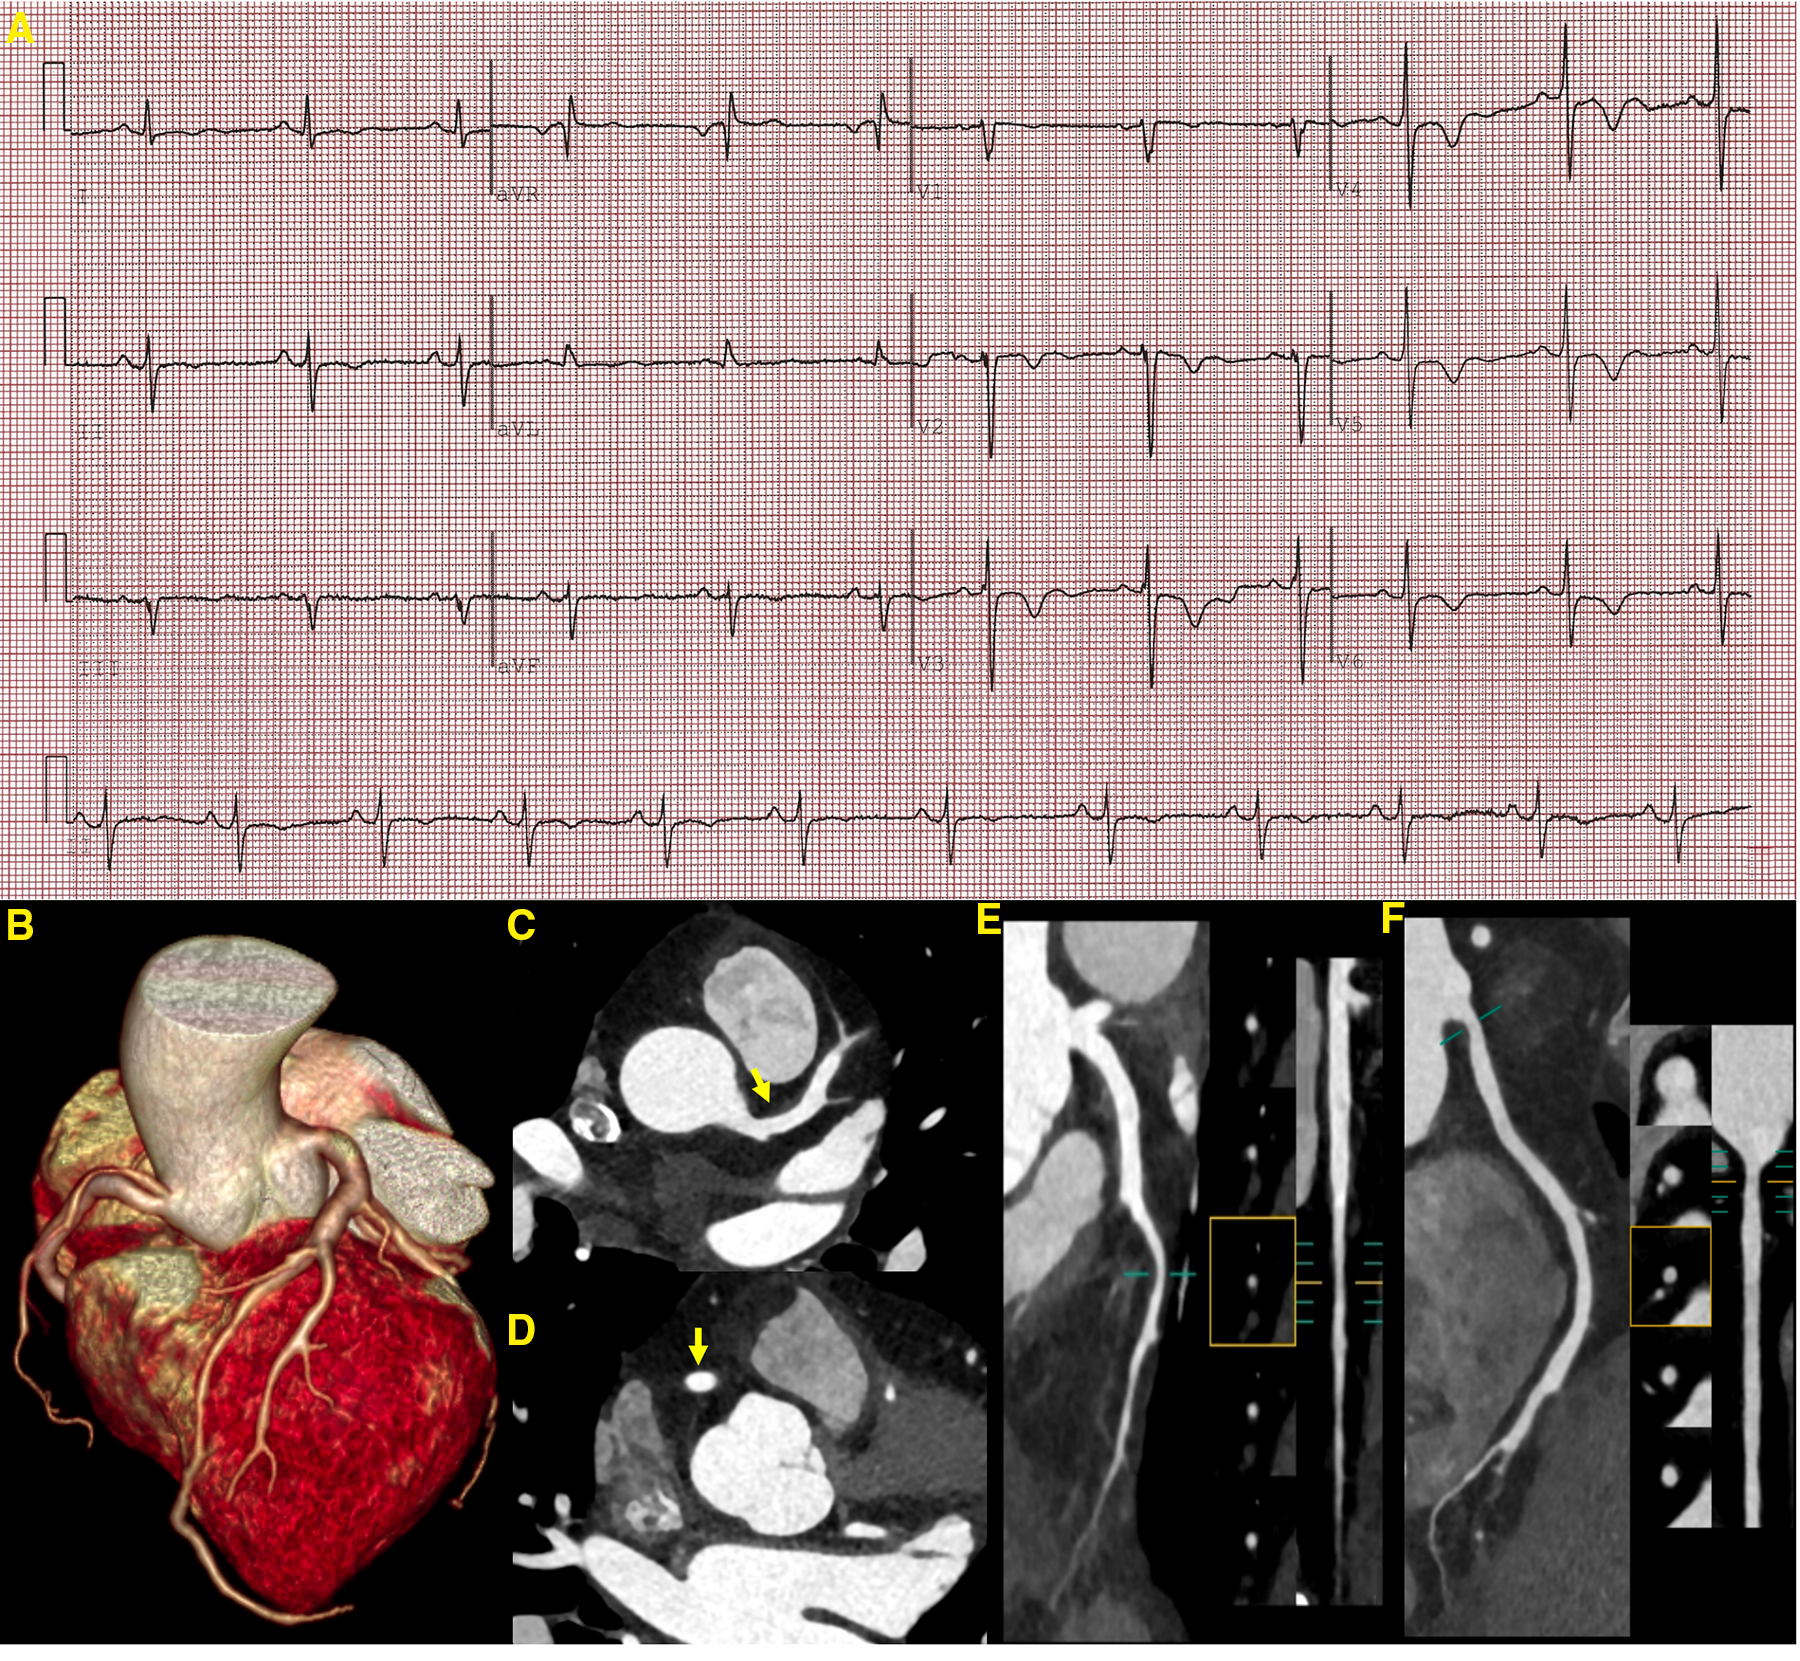

Figure 3

ECG and CCTA images demonstrating a sinus rhythm, a left deviation of the electrical axis, inverted T waves, and poor R-wave progression (A). A three-dimensional volume-rendered image (B) shows normal coronary artery alignment with continuous lumen. Axial images (C,D) show a mild diffuse dilatation of the LAD artery and RCA, with maximum diameters of 4.5 mm in the LAD artery and 4.7 mm in the RCA (yellow arrow). A curved planar reformation (E,F) demonstrates a non-calcified plaque in the proximal segment of the LAD artery and RCA with mild luminal narrowing. LAD, left anterior descending; RCA, right coronary artery.

Given the patient’s clinical features and history, ECG, TTE, and CMR, a diagnosis of Leopard syndrome was highly likely (5). A supplemental genetic testing revealed a heterozygous missense mutation in the PTPN11 gene (c.836A>G, p.Tyr279Cys), confirming its suspicion. Medical therapy (metoprolol or verapamil) was recommended to minimize cardiac burden and alleviate exertional dyspnea. For the multiple lentigines, intense pulsed light therapy was advised (7). However, the patient insisted that her current clinical presentation was not severe enough to affect her daily life and therefore refused further treatment with full awareness of the adverse cardiovascular events that may occur. We followed up the patient closely, and after 3 months, she developed transient chest pain that resolved spontaneously. Cardiac biomarkers such as troponin T (0.047 ng/ml), troponin I (0.051 g/L), creatine kinase isoenzyme (12 U/L), and natriuretic peptide (12 pg/ml) did not show any significant abnormality in the first 24 h after admission. A supplemental CCTA revealed minor non-calcified plaques in the left anterior descending artery and right coronary artery with mild luminal stenosis, which was unlikely to cause episodes of chest pain. In addition, a mild diffuse dilatation of the left anterior descending and right coronary arteries was noted (Figure 3). However, apical hypertrophy was unchanged from the CMR imaging study performed three months earlier (Figure 2). Unfortunately, the patient again refused further treatment (Table 1).